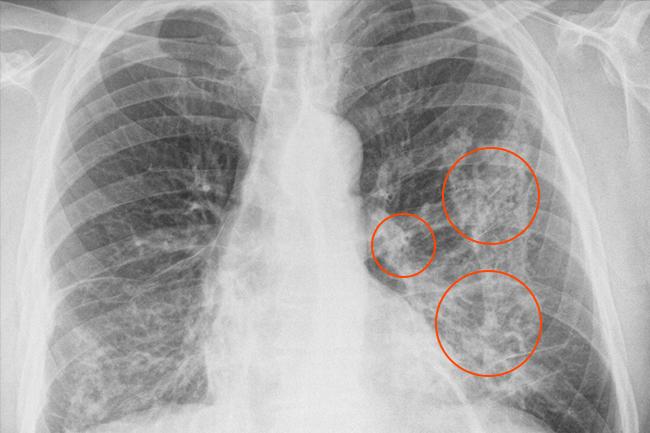

Плеврод спайки — это наблюдаемое на флюорографии явление, при котором на дыхательной пленке (плевре) образуются спайки. Спайки могут возникать как на одной, так и на обеих сторонах легких, что может быть индикативным признаком различных заболеваний легких.

Для установления точного диагноза и определения причины плеврод спаек у ребенка может потребоваться комплексное обследование, включающее в себя флюорографию, компьютерную томографию (КТ) и другие методы исследования легких.

— рентгенологическое исследование с помощью флюорографии;

— рентгенография для выявления заболеваний;

— компьютерная томография (КТ) для получения детальных изображений;

Во второй фазе плеврита при воспалении образуются спайки в плевре, что нарушает отток жидкости. Если лечение не назначено или не дает ожидаемых результатов, то плевральная жидкость и гной начинают накапливаться в плевральной полости.